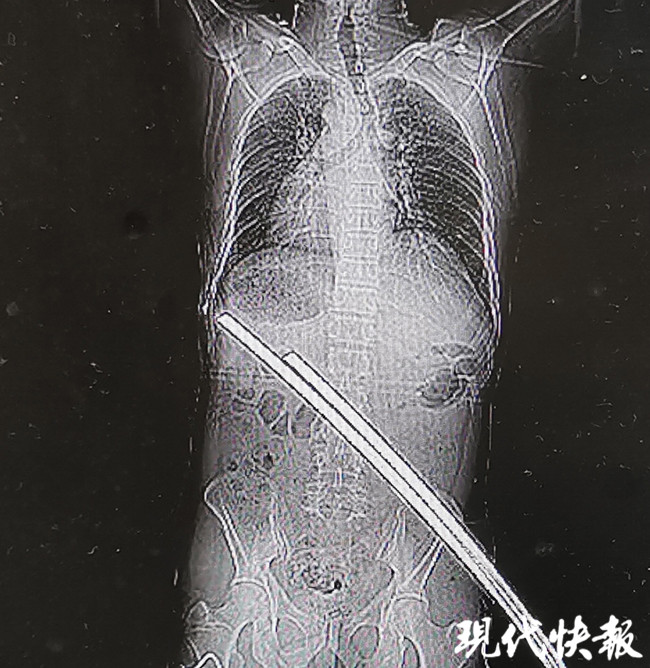

△兩根鋼筋刺穿張師傅腰部

△刺穿張師傅身體的兩根鋼筋

通過(guò)CT檢查,醫(yī)生稱鋼筋只是刺穿張師傅的肌肉,萬(wàn)幸的是并未累及身體重要臟器和血管,除此以外,張師傅肋骨骨折、左肘部皮膚擦傷,無(wú)生命危險(xiǎn)。經(jīng)過(guò)兩個(gè)小時(shí)的急診手術(shù),鋼筋從張師傅右臀部被拔除,手術(shù)一切順利。